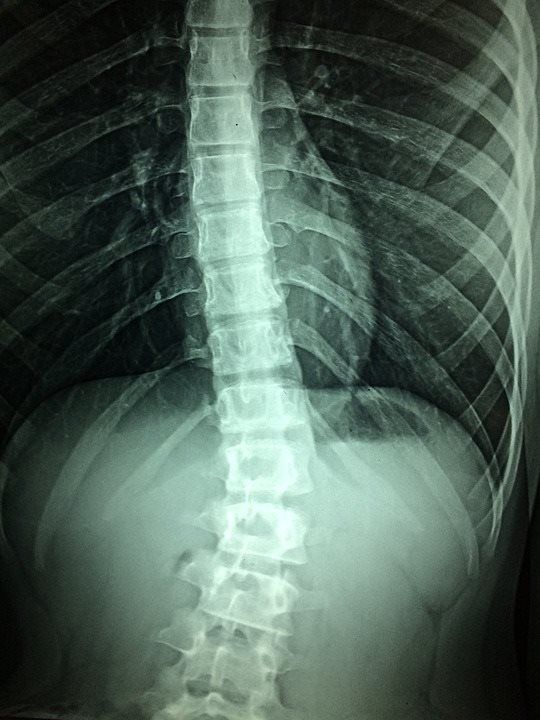

Our primary focus is Interventional Pain Management.

We approach each patient as an individual.